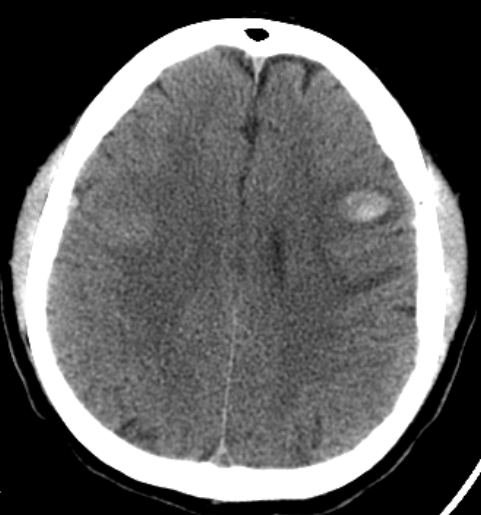

La angiotomografía cerebral evidencia la presencia de múltiples áreas hiperdensas de distribución difusa, bilateral que compromete ambos lóbulos frontales, compatibles con hemorragias intraparenquimatosas de focos múltiples, asociado a edema perilesional (Fig 1 y 2), además se identificó la presencia de signo del delta vacío secundario a trombosis venosa dural que compromete el seno sagital superior, con extensión a la confluencia de los senos, seno transverso derecho, así como el seno yugular y vena yugular ipsilateral (Fig 3 y 4).

FIGURA 1,2. Imágenes de angiotomografía cerebral en proyección axial y sagital, en ventana de cerebro que muestra la presencia de múltiples áreas hiperdensas en lóbulos frontales, de distribución difusa, bilateral.